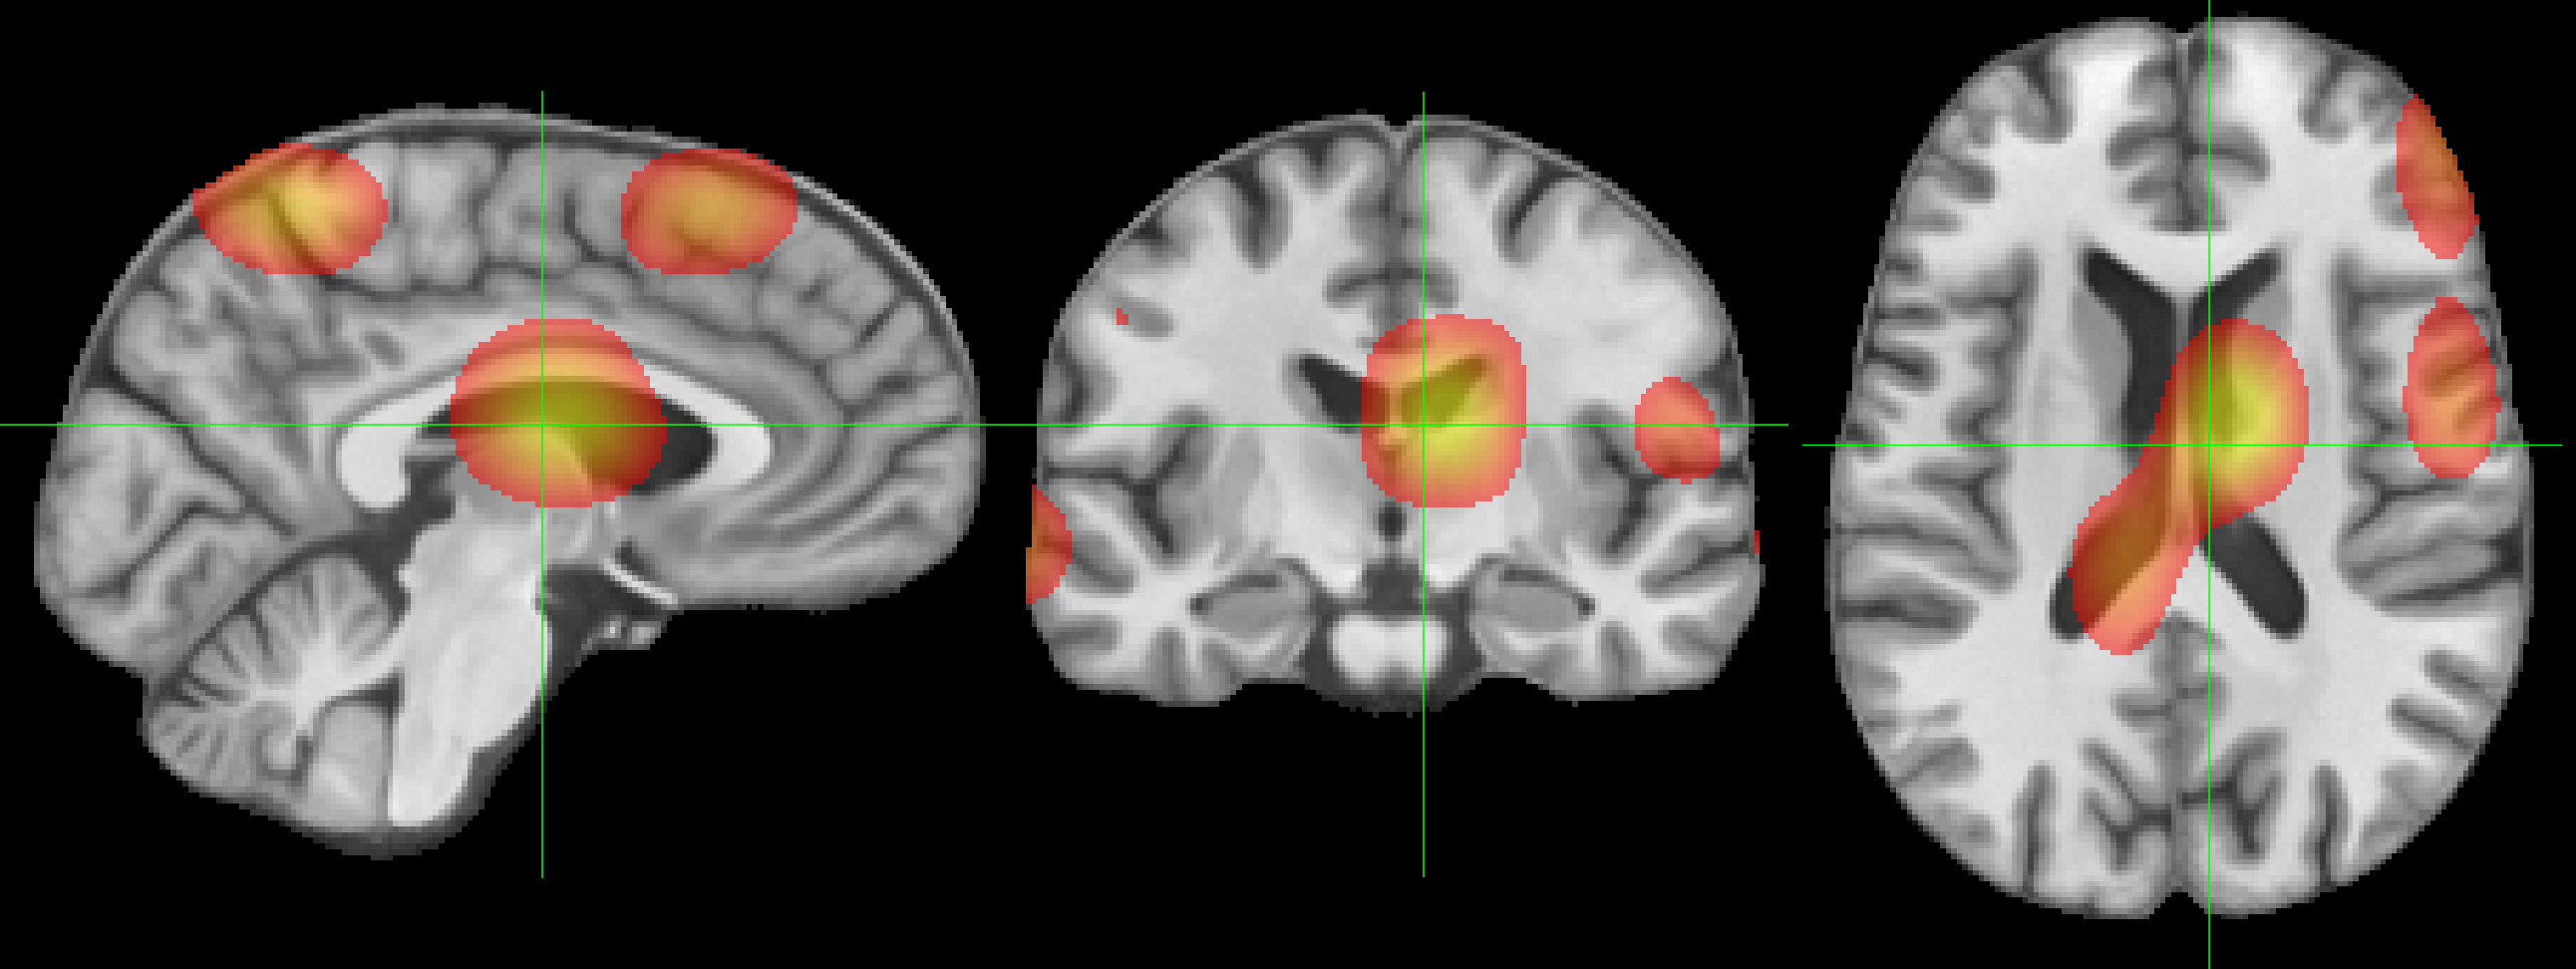

Refer to caption

(b) MINiT Attention Map

Refer to caption \phantomcaption

Figure 6: Attention maps learned by (a) NiT and (b) MINiT models. The bar shows the color-map (from red =0.4absent0.4=0.4 to yellow =0.8absent0.8=0.8; thresholded on the lower bound for clarity).

We compute the attention maps for the base NiT from the output token to the input space using Attention Rollout [1]. For MINiT, we use Attention Rollout to calculate attention weights for each patch in a block, which we concatenate and then average to build attention weights for a block. We proceed to use Attention Rollout using the block attention weights to compute the final attention maps. From Fig. 6, we observe that MINiT attends between numerous different voxels in the neuroimage (due to MIL nature), in contrast to the focused attention between fewer, but larger, voxels by the base NiT. Considering existing documented evidences [21] that sex differences in youth are widespread in the brain and the significant difference in accuracy between the two models, it is evident that MINiT is able to better generalize by capturing features spread all around the brain.